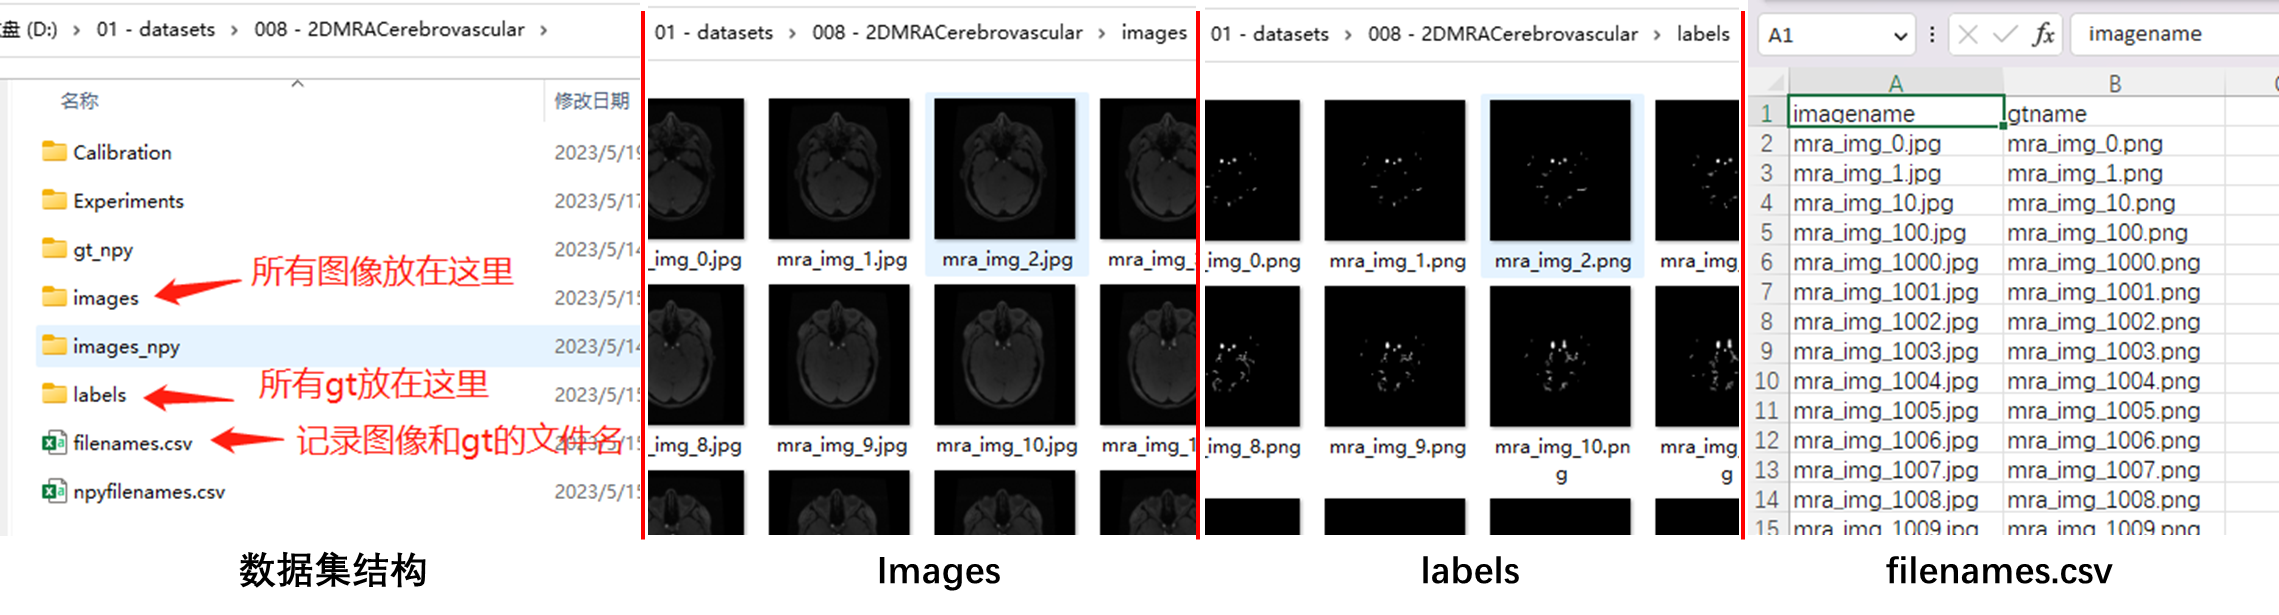

- 数据集来自2022年发表在TMI的论文《Attention-Assisted Adversarial Model for Cerebrovascular Segmentation in 3D TOF-MRA Volumes》。数据集实际上是MRA图像,我这里只保留了脑血管GT,用二分类的Unet来介绍整体的部署流程(这里感谢诺师弟的帮助)。

- UNet相关的训练测试代码基于hust-linyi/MedISeg,本博客相关的Unet代码上传在projects/torchdnn/demos/unet,执行相关脚本时,请保证文件根目录为

projects/torchdnn。 - 本博客相关的代码上传在百度云(提取码:0a09 )中的

datasets/008 - 2DMRACerebrovascular.zip文件夹中。

此外,这里介绍下数据集格式和训练测试的脚本,如果各位有需求,可以训练自己的数据集。其中csv文件的生成利用了pandas,生成文件部分的代码如下所示。如果需要修改数据集加载方式的话修改dataloaders/dataload.py中class DataFolder。目前这套代码仅支持二分类问题,其他任务的支持请关注torchdnn文件夹里面的README。

import pandas as pd

csvpath = os.path.join(dsroot, "filenames.csv")

csvlist = list(zip(imgnames, gtnames))

filenamefile = pd.DataFrame(data=csvlist, columns=['imagename', 'gtname'])

filenamefile.to_csv(csvpath, index=False)